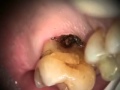

Възстановителна Дентална МедицинаПострояване на релеф на молар с I клас кавитетВидяно: 6422 пъти | Коментари: 0 |

Възстановителна Дентална МедицинаЛечение на карис на фуркациятаВидяно: 3879 пъти | Коментари: 0 |

ЕндодонтияЛечение на многоканален долен моларВидяно: 4185 пъти | Коментари: 0 |